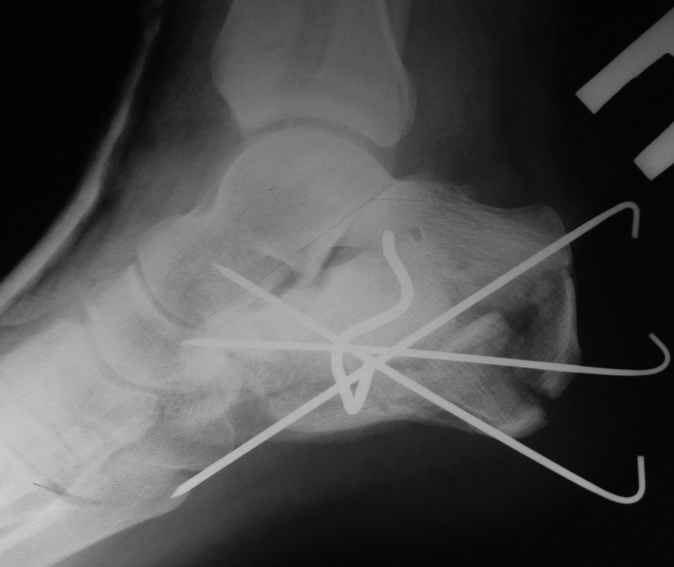

представляю снимки пациента с переломом пяточной кости. послеоперационный снимок этапный - по снятии швов спицы удаляю и наладываю циркулярную гипсовую повязку. к сожалению снимки с удаленной скобой представить не могу но поверьте на слово - консолидация полная, коррекция стойкая.